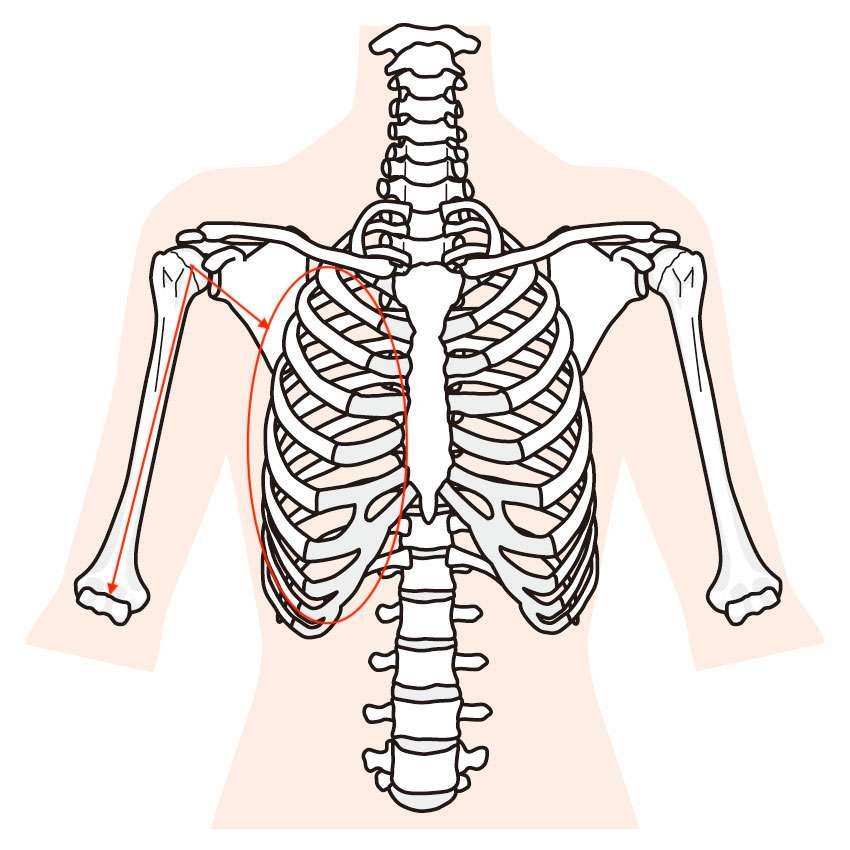

上記の図をご覧いただくと、赤丸と赤の矢印で示したものがあります。

体の正面から見ている図になります。

赤丸で示したところが肋骨になりますが、胸椎や右側肋骨に可動性低下や歪みがあると、上腕骨頭(肩)が赤の矢印の方向に引っ張られるチカラが働きます。

そして、右肘関節や右手関節周囲組織(筋肉や靭帯)の柔軟性低下すると、上腕骨頭(肩)が赤の矢印の方向へ引っ張られます。

そうすると、上腕骨頭(肩)が肩関節の正しい位置からズレてしまうので、その状態のまま動かしてしまうと、肩関節のところで骨同士が衝突してしまったり、肩関節周囲の神経や血管、靭帯、筋肉組織などを巻き込んでしまうことで刺激を受けて痛みが発生してしまうみたいなことが起こってしまうわけです。